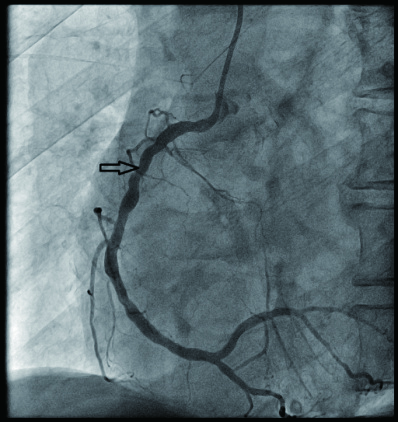

病例2 3(图 6~8 LAD近段 次全闭塞 2级 LAD近段植入支架1枚

图 6 病例2冠脉造影示LAD中段病变

图 7 病例2冠脉造影示LCX病变

图 8 病例2冠脉造影示RCA病变